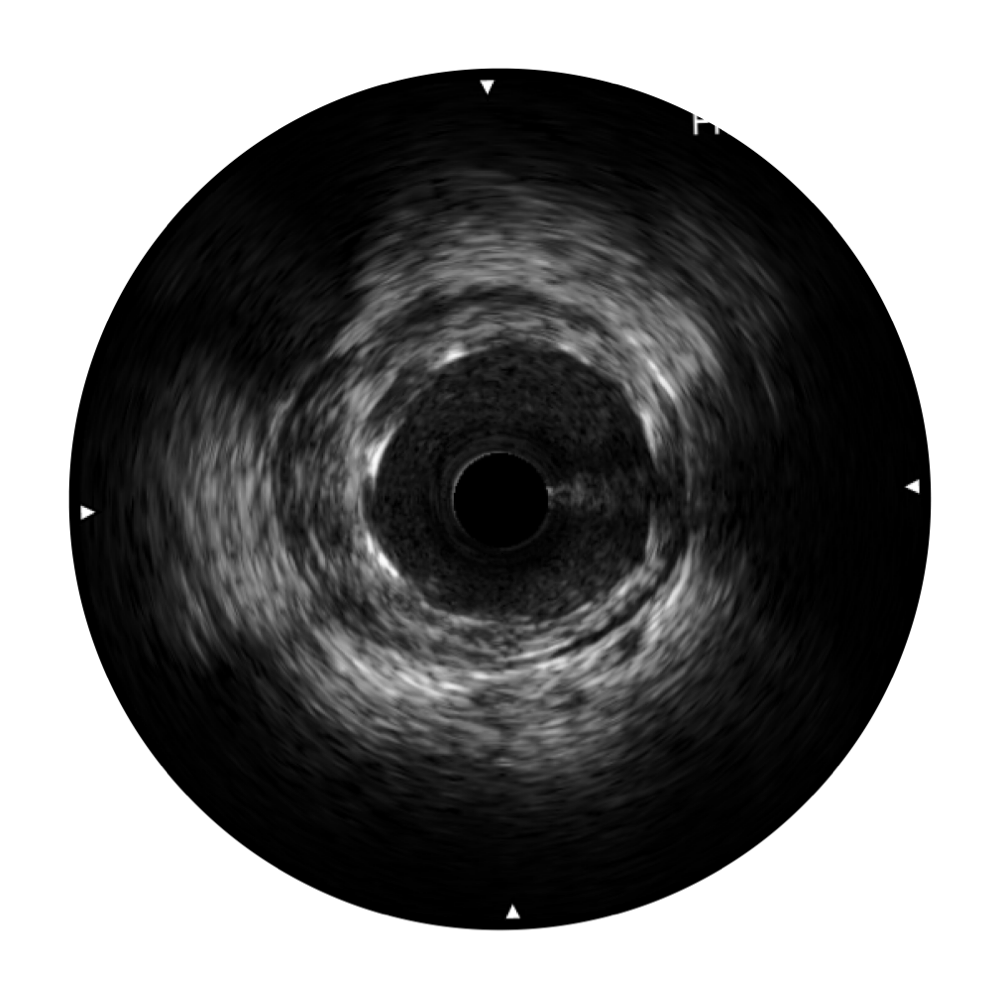

传统IVUS图像

对比传统IVUS导管成像,九州酷游宽频IVUS图像的近场支架梁显影更细腻,远场中膜外血管仍清晰可辨,兼顾远中近,兼顾分辨力与穿透深度